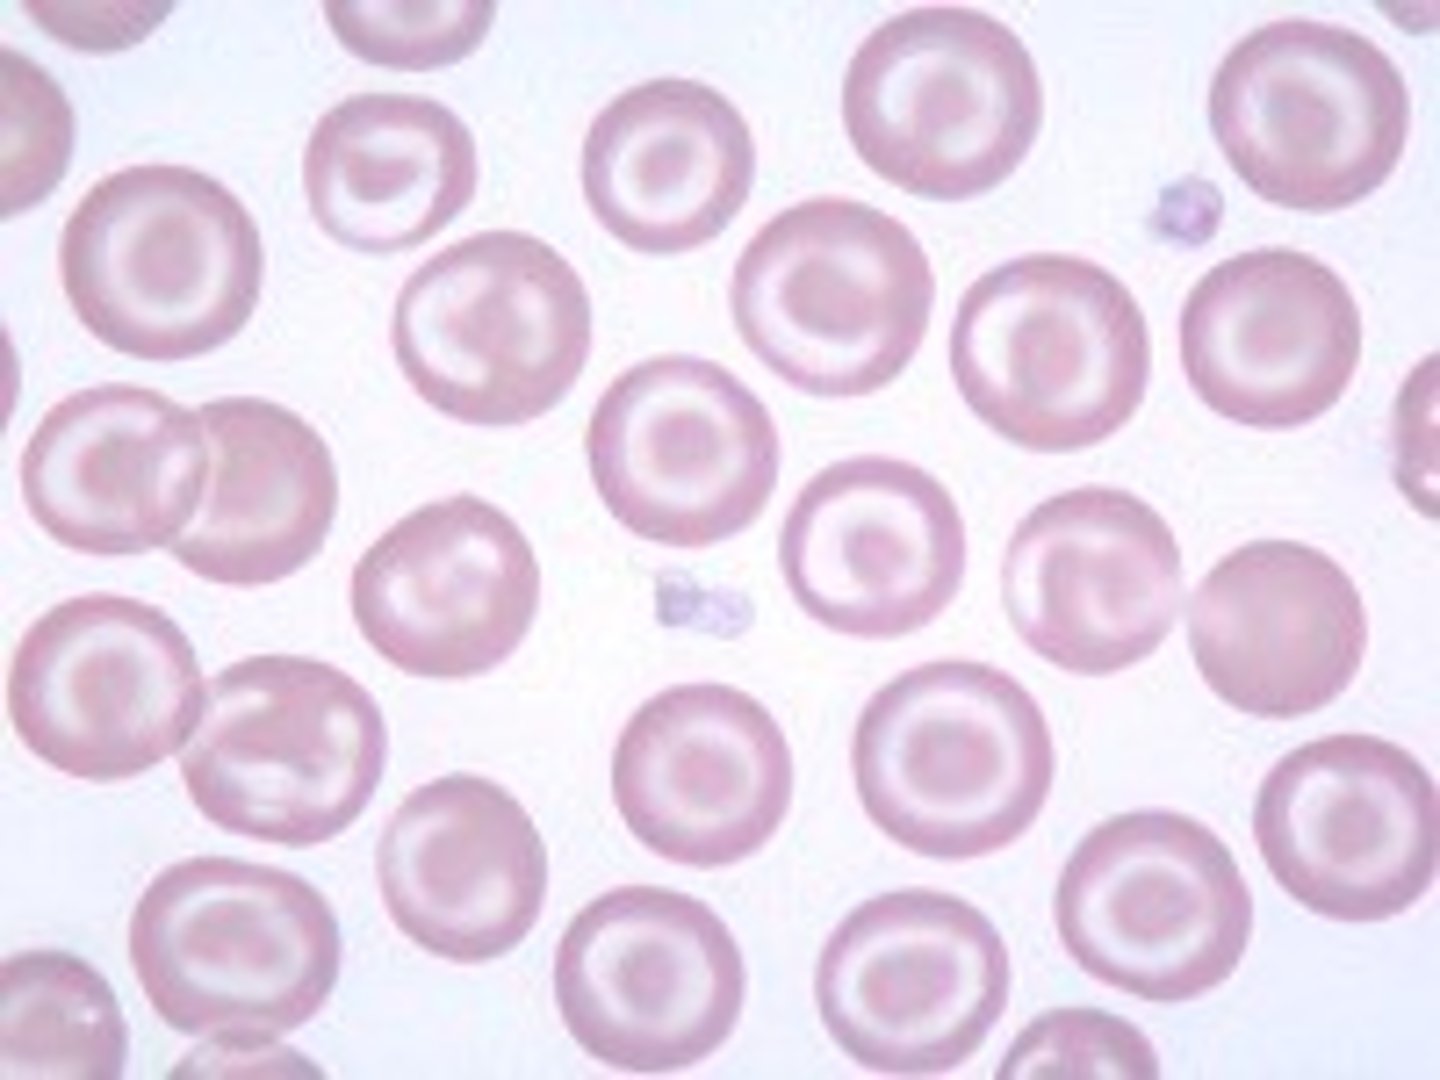

hypochromasia

increased level of central pallor

-decrease hemoglobin concentration